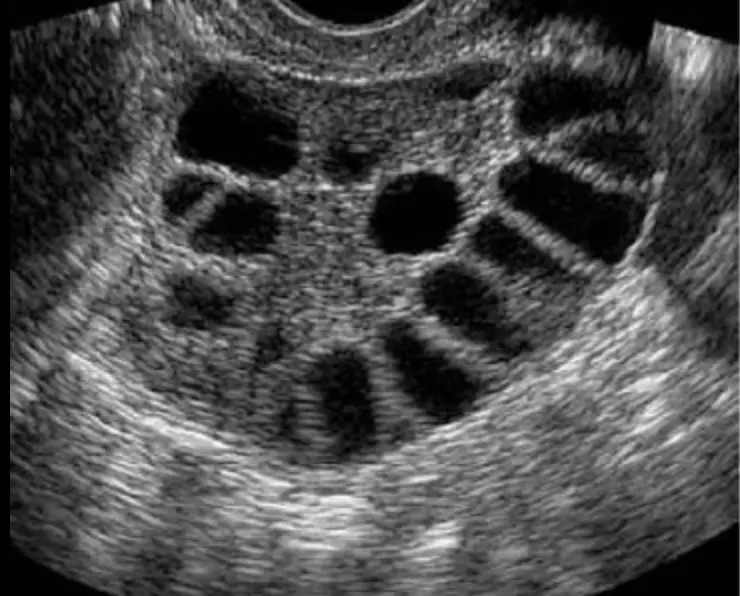

Ovaries: The scan assesses the size and presence of cysts. During the assessment, we will assess the number of antral follicles and follicle sizes.

It involves an internal ultrasound to measure the number and size of the follicles in each ovary. The first scan will often occur several days before ovulation is expected and continue every 2-3 days until the follicles (eggs) are the correct size for your specific fertility treatment.